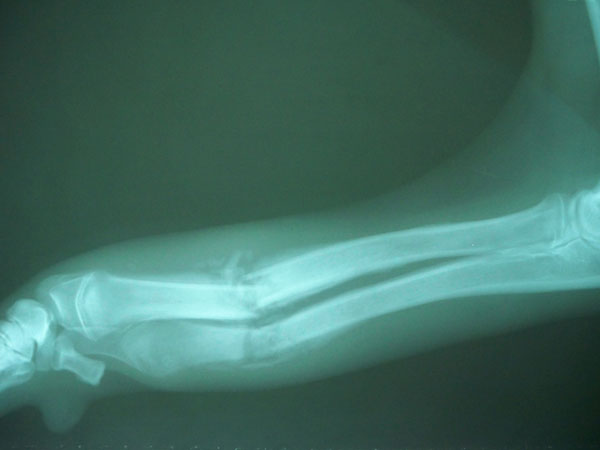

Ελληνικός ποιμενικός 7 μηνών με κάταγμα στο αντιβράχιο.

Χειρουργήθηκε και είναι απολύτως φυσιολογικό. Οι ακτινογραφίες είναι πριν και μετά το χειρουργείο.

Τσοπανόσκυλο 7 μηνών με 2 εβδομάδων τέλειο κάταγμα κάτω τρίτου μεσότητας διάφυσης αριστερής κερκίδας και ωλένης.